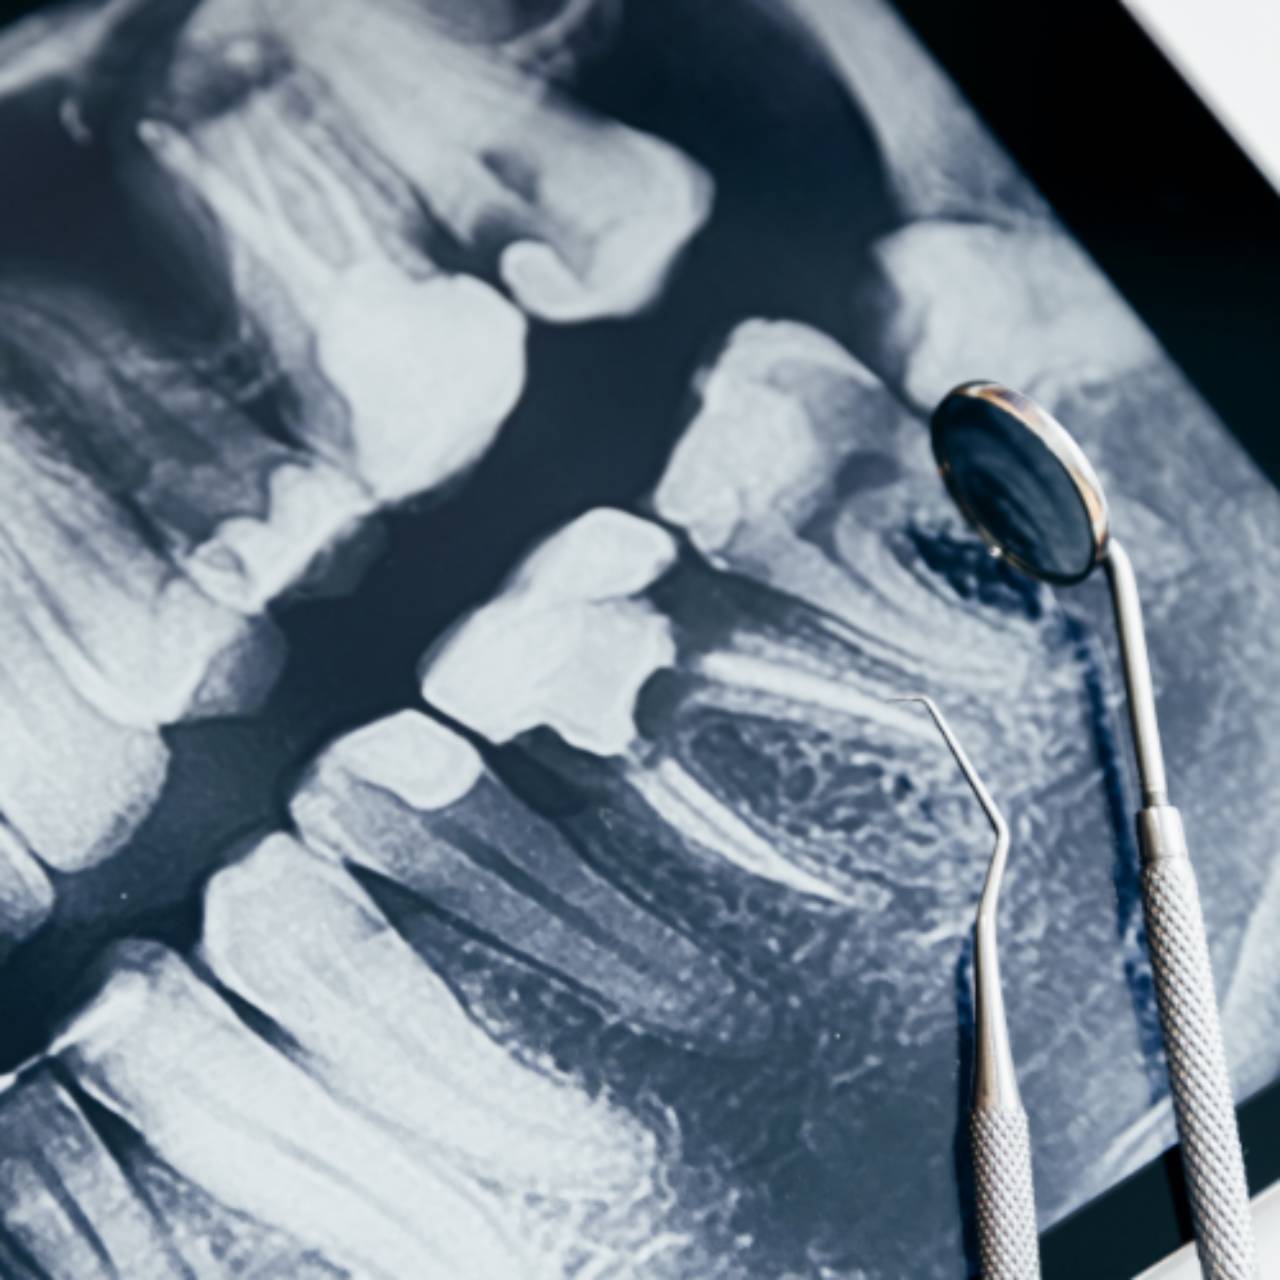

Estética OdontológicaO Rx Interproximal oferecido pela Radiodoctor em Lençóis Paulista, SP, é a solução ideal para dentistas que buscam imagens detalhadas e precisas das regiões interdentais. Este exame radiográfico é amplamente utilizado para a detecção de cáries entre os dentes, permitindo um diagnóstico precoce e preciso de problemas que podem não ser visíveis a olho nu. Com nossa tecnologia avançada, garantimos imagens nítidas e detalhadas, fundamentais para tratamentos odontológicos mais eficazes.

O Rx Interproximal é uma ferramenta indispensável no planejamento de tratamentos odontológicos, como restaurações, limpezas profundas e tratamentos de cárie, oferecendo uma visão clara e detalhada das estruturas dentais e seus espaços interdentais.

Alta precisão: O exame fornece imagens de alta resolução, garantindo a visualização clara das áreas entre os dentes, onde a detecção de cáries e outras lesões é mais difícil.